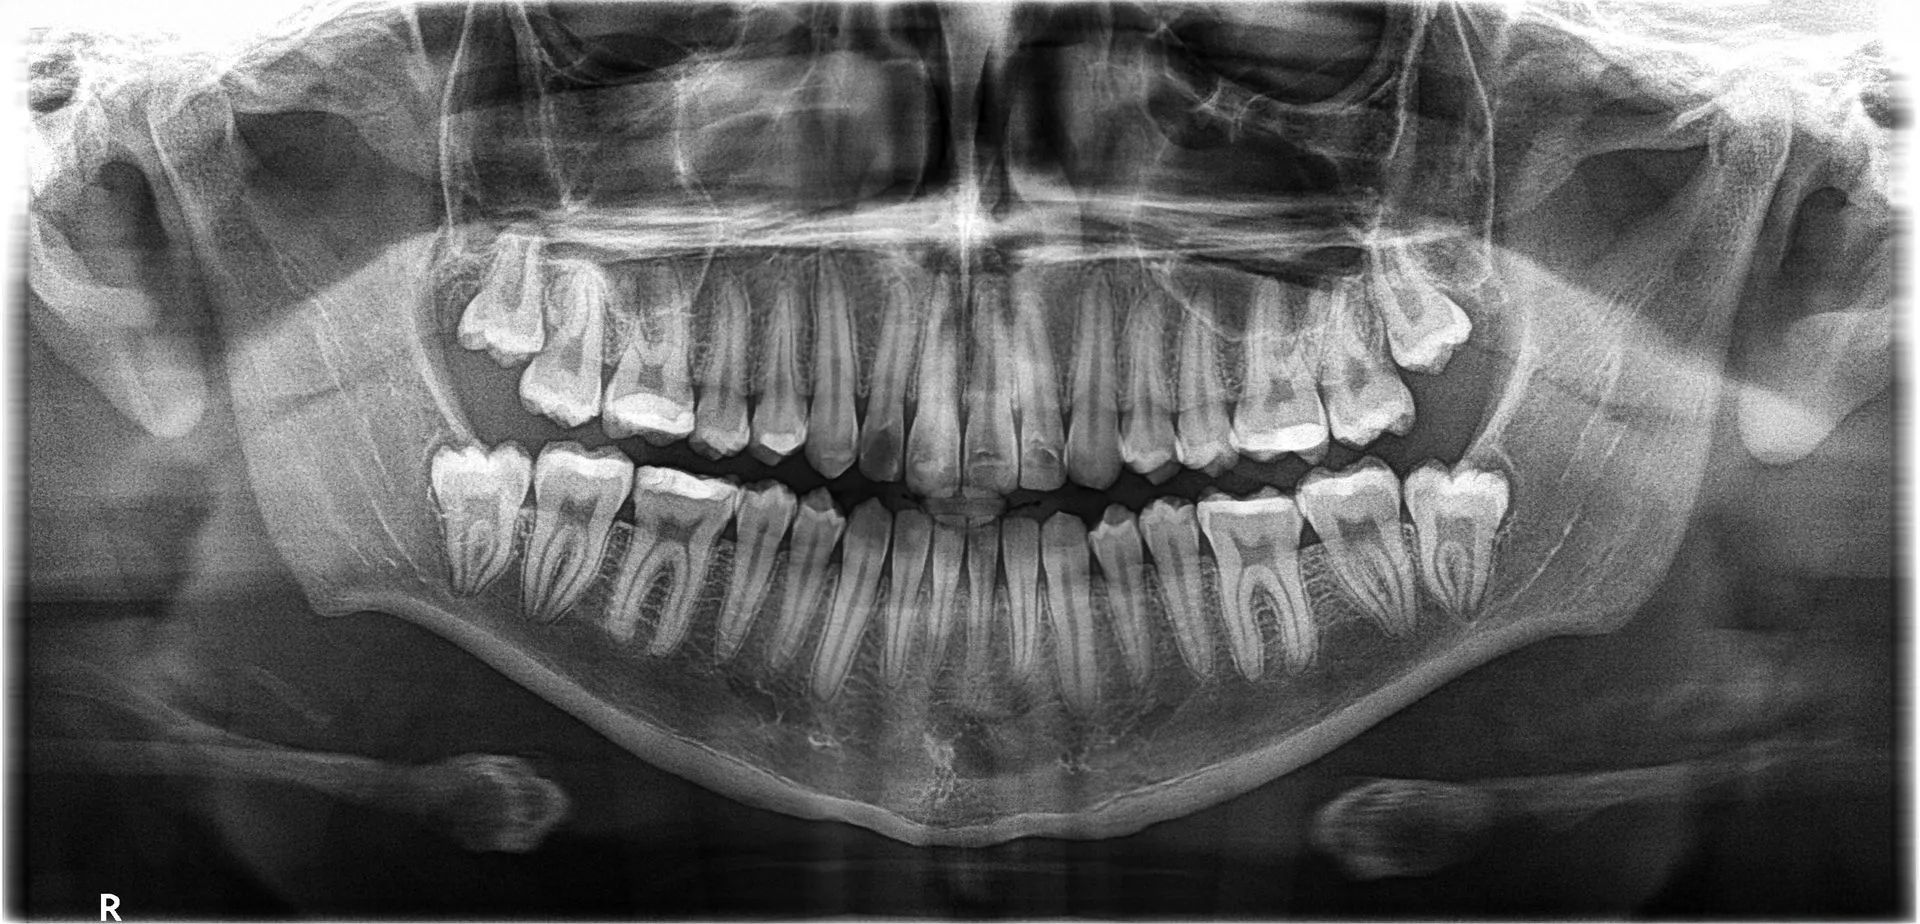

Uno de nuestros principales servicios es la adquisición de imágenes dentales 2D y 3D, fundamentales para un diagnóstico preciso y una planificación adecuada de tratamientos dentales.

Contamos con tecnología avanzada que nos permite obtener imágenes claras y detalladas de la boca y los tejidos circundantes, lo que es crucial para evaluar la salud dental y detectar posibles problemas.